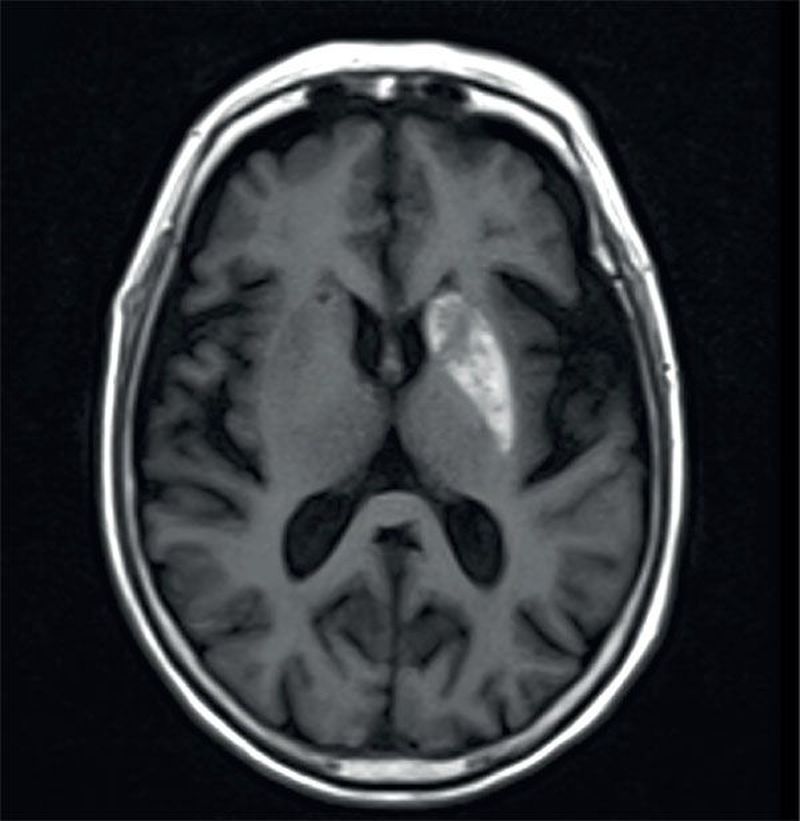

A 62-year-old woman had a 4-week history of sudden onset of involuntary hemichoreiform. She had been diagnosed with type 2 diabetes 10 years earlier and her blood glucose had been poorly controlled. Based on the MRIs, what is the most likely diagnosis? a)Intracranial tumour b)Ischaemic cerebral infarction c)Demyelinating disease d)Diabetic hemichorea